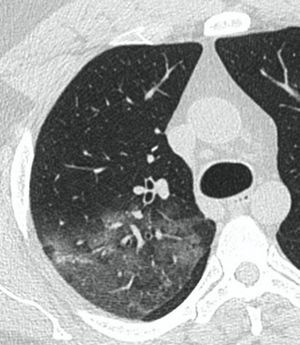

КТ имеет высокую чувствительность в выявлении изменений в легких, характерных для COVID-19. Применение КТ целесообразно для первичной оценки состояния ОГК у пациентов с тяжелыми прогрессирующими формами заболевания, а также для дифференциальной диагностики выявленных изменений и оценки динамики процесса. КТ позволяет выявить характерные изменения в легких у пациентов с COVID-19 еще до появления положительных лабораторных тестов на инфекцию с помощью МАНК. В то же время, КТ выявляет изменения легких у значительного числа пациентов с бессимптомной и легкой формами заболевания, которым не требуется госпитализация. Результаты КТ в этих случаях не влияют на тактику лечения и прогноз заболевания при наличии лабораторного подтверждения COVID-19. Поэтому массовое применение КТ для скрининга асимптомных и легких форм болезни не рекомендуется.

3. Применение лучевых методов у пациентов с симптомами ОРВИ легкой степени тяжести и стабильном состоянии пациента, возможно только по конкретным клиническим показаниям, в том числе при наличии факторов риска, при условии достаточных технических и организационных возможностей. Методом выбора в этом случае является КТ легких по стандартному протоколу без внутривенного контрастирования или РГ при ограниченной доступности КТ. Использование УЗИ в этих случаях нецелесообразно. Применение КТ исследования в сроки ранее 3 - 5 дней с момента появления симптомов заболевания является нецелесообразным.

4. Все выявляемые при лучевых исследованиях признаки, включая КТ-симптомы, не являются специфичными для какого-либо вида инфекции и не позволяют установить этиологический диагноз. Вне клинической (эпидемической) ситуации они не позволяют отнести выявленные изменения к пневмонии COVID-19 и дифференцировать их с другими пневмониями и невоспалительными заболеваниями. Данные лучевого исследования не заменяют результаты обследования на РНК SARS-CoV-2. Отсутствие изменений при КТ не исключают наличие COVID-19 и возможность развития пневмонии после проведения исследования.

5. Рекомендовано проведение лучевого исследования пациентам при среднетяжелом, тяжелом и крайне тяжелом течении ОРИ с целью медицинской сортировки, оценки характера изменений в грудной полости и определения прогноза заболевания:

- выполнение КТ легких без внутривенного контрастирования в стационарных условиях или в амбулаторных - при показаниях к госпитализации;